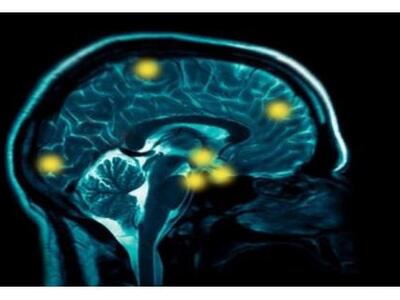

Η ανάπτυξη ενός τεστ αίματος που θα προβλέπει έγκαιρα τη νόσο Αλτσχάιμερ, αρκετά χρόνια πριν εμφανιστούν τα πρώτα συμπτώματα, αποτελεί βασικό ζητούμενο από την ιατρική κοινότητα. Όπως ανακοίνωσε διεθνής ομάδα επιστημόνων, μεταξύ των οποίων μία Ελληνίδα ερευνήτρια, έκαναν ένα πολύ σημαντικό βήμα προς αυτή την κατεύθυνση, ανακαλύπτοντας σειρά από βιοδείκτες (πρωτεϊνες) στο αίμα, που προβλέπουν με ακρίβεια 87% την έναρξη της άνοιας του εγκεφάλου.

Οι επιστήμονες διευκρίνισαν πάντως ότι, προς το παρόν, το τεστ δεν είναι έτοιμο για ιατρική χρήση. Θα χρειαστούν ορισμένα ακόμη χρόνια ερευνών και κλινικών δοκιμών σε μεγαλύτερες ομάδες των 5.000 έως 10.000 ατόμων, εωσότου η διαγνωστική ακρίβεια του τεστ βελτιωθεί (σε πάνω από 90%), προκειμένου να είναι έτοιμο για ευρεία κλινική χρήση. Σε κάθε περίπτωση, ένα μελλοντικό τεστ αίματος θα συνδυάζεται με άλλες πιο ακριβές και πιο επεμβατικές διαγνωστικές μεθόδους, όπως η απεικόνιση του εγκεφάλου και ο έλεγχος του εγκεφαλονωτιαίου υγρού.

Μια βασική αιτία γι αυτή την αποτυχία είναι ότι η νόσος διαγιγνώσκεται με μεγάλη καθυστέρηση, όταν πια οι εγκεφαλικές βλάβες είναι μη αναστρέψιμες, με συνέπεια τα όποια φάρμακα να μην είναι ιδαίτερα αποτελεσματικά. Αυτό εξηγεί γιατί οι επιστήμονες θεωρούν ύψιστη προτεραιότητα να βρουν επιτέλους μια απλή μη επεμβατική διαγνωστική εξέταση, όπως ένα τεστ αίματος που θα κάνει έγκαιρη διάγνωση - κάτι όμως που επίσης έχει αποδειχτεί πολύ δύσκολο μέχρι σήμερα.